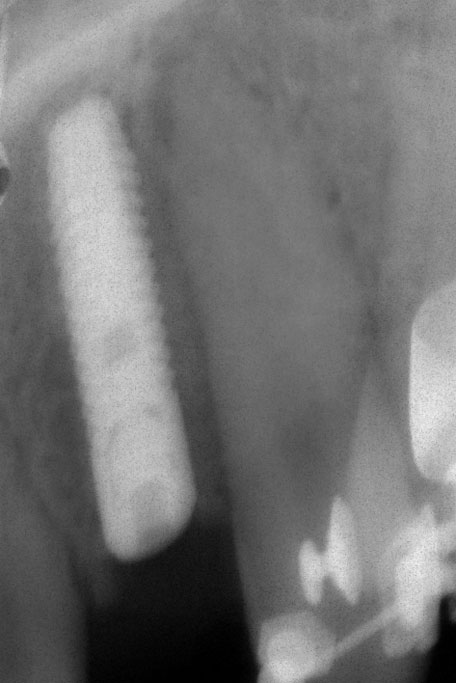

Die Nichtanlage der seitlichen oberen Schneidezähne und der zweiten unteren kleinen Backenzähne (Prämolaren) ist relativ häufig.